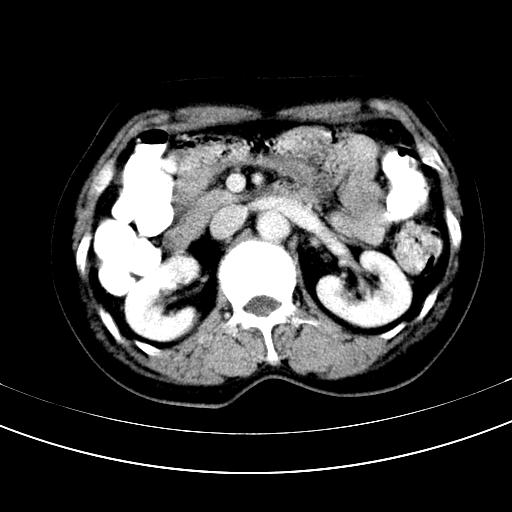

标题: CT12767:肝脏病变请会诊

补充强化片

胃内见充盈缺损,建议行胃镜病理检查,如果胃内无占位,则肝内考虑左叶、尾叶为包膜型肝癌,如有则考虑为转移瘤

胃内见充盈缺损,建议行胃镜病理检查,如果胃内无占位,则肝内考虑左叶、尾叶为包膜型肝癌,如有则考虑为转移瘤,左侧肾上腺 明显增大,成结节改变,本人考虑转移瘤可能性大。

胃内的充盈缺损因胃壁不厚,我个人考虑为胃内残留物。肝左叶及尾叶病灶,我首先考虑血管瘤,其次为肝癌。(尾叶的更低密度区太规整)

肝脏左叶和尾叶均见略低密度影,尾叶病变内见坏死?其边界清晰,形态规整1血管瘤,2肝癌待排

胆囊内见一略高密度影,息肉?

1.肝左叶及尾叶占位建议增强2.肝硬化

肝脏左叶和尾叶均见略低密度影,尾叶病变内见坏死?其边界清晰,形态规整1血管瘤,2肝癌待排3建议增强。

胃内充盈缺损考虑为胃内存留物,肝左叶和尾状叶两个病灶,均为低密度,建议增强。

考虑:胃体小弯侧胃癌(或平滑肌瘤恶化或平滑肌肉瘤)伴肝转移,左侧肾上腺转移不除外.

胃内充盈缺损考虑为肿瘤,肝尾叶及左叶肿块考虑转移瘤

胃癌肝内转移及肾上腺转移。

胃窦部占位伴肝及左肾上腺转移可能大,建议增强扫描。

肝脏左叶和尾叶均见略低密度影,尾叶病变内见坏死?其边界清晰,形态规整1血管瘤,2肝癌待排3建议增强或结合临床及超声与实验室检查

肝左叶及尾叶低密度灶,增强有渐进性明显强化,考虑血管瘤。胃内“充缺”首先要排除异物(食物),变换体位可鉴别。增强时机抓的不好,还应该有延时像。

谢谢楼主的增强片子,平扫没发现左侧肾上腺的问题很不好意思,可惜片子只有门脉期,所以还只有猜,肝脏的病灶在门脉期部分强化,首先考虑为血管瘤(其他的用一种病不好解释)胃要喝水就好了现在不好说是否有问题,左肾上腺的问题考虑是肿瘤。

做了增强后,可以明确胃是没有肿瘤的,肾上腺也没有肿瘤.肝左叶的病灶首先考虑血管瘤,应该再延迟,肝尾状叶的病灶仍不能排除肝癌的可能性.